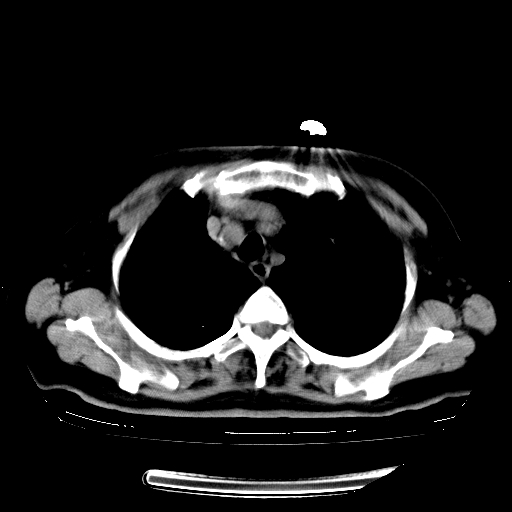

女,70岁,咳嗽、咳痰一个月,低热一周。

1.左上肺结核,部分纤维化。右肺中下叶部分肺不张,内见液化、坏死及点状钙化,右中下叶支气管壁增厚、管腔狭窄,见多个点状钙化,结合临床考虑支气管内膜结核,建议痰检查抗酸杆菌并参考血沉。两肺多个小圆点状高密度灶,境界模糊,多考虑结核肺内播散。但本人年龄较大首先应支气管镜检以除外右肺癌。

2.胸主动脉夹层。

1、右肺占位,考虑周围型ca 。

2、右下肺软组织密度肿块影,考虑肺隔离征。